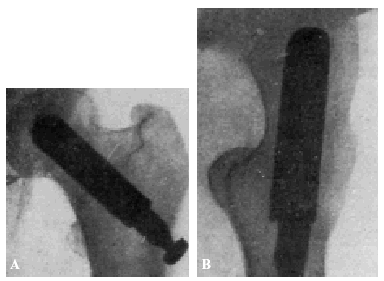

El pronóstico era desfavorable, quo ad functionem, porque estas fracturas, tratadas por los métodos clásicos, daban lugar, indefectiblemente, a una seudoartrosis en un porcentaje superior a un 90 por 100. Se exceptúan de esta evolución desfavorable las fracturas enclavadas en abducción (fig. 1), las cuales consolidan siempre aunque no se aplique ningún tratamiento.

Figura 1. Fractura enclavada en abducción. Las fracturas de este tipocuran bien sin ningún tratamiento.